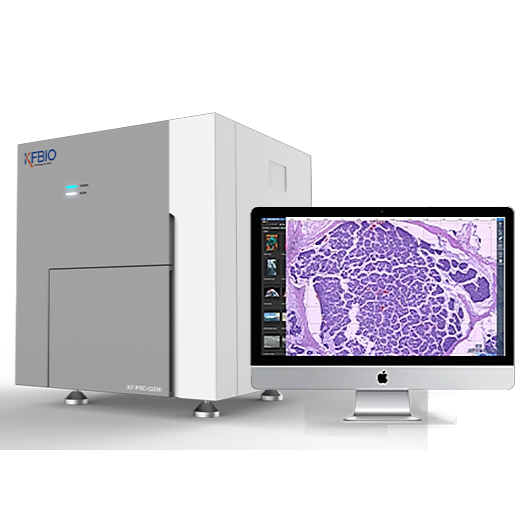

Digital Pathology Slide Scanner (PRO)

Digital Pathology Slide Scanner (PRO)

High Image Quality for Digital Pathology

KFBIO Digital Pathology Slide Scanner (PRO) is a world leader in the accuracy of movement, focus, and image processing, and its accurate whole slide imaging not only meets the requirements of digital slide viewing and operation but is also suitable for AI-assisted image analysis.

High Quality, 3 Colors Independent Processing

K-SCP color processing method helps restore the original color, saturation, color temperature, color contrast and other indicators to enhance images, as well as color compensation of different displays after imaging.

High Resolution, 0.5µm/pixel (20X), 0.25µm/pixel (40X)

It adopts top optical accessories. The light source, objective lens, camera, optical path and other accessories are comprehensively optimized. It greatly improves the optical resolution to directly observe the structure and details in the cell. The nucleus edge is sharp and the internal structure is clearly visible. The resolution distance can be as small as 0.125µm.

High Precision, 20nm Fine Control, 80x magnification

Linear magnetic axis drive and grating ruler positioning mechanism are adopted to achieve ultra-high precision of image movement control and image positioning at the nanometer level. It helps sample fast and accurately to achieve stable imaging for a longer period of time. The magnification can reach 80x.